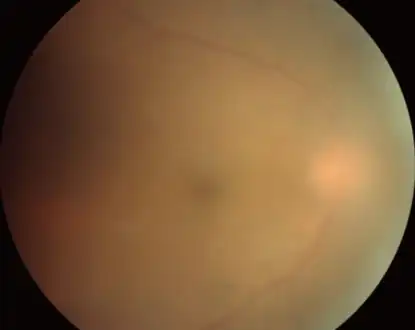

Fundus image of choroidal neovascularization in ocular toxoplasmosis

Infection of the vitreous body in toxoplasmosis of the eye

Acute toxoplasmosis is often asymptomatic in healthy adults.[13][14] However, symptoms may manifest and are often influenza-like: swollen lymph nodes, headaches, fever, and fatigue,[15] or muscle aches and pains that last for a month or more. It is rare for a human with a fully functioning immune system to develop severe symptoms following infection. People with weakened immune systems are likely to experience headache, confusion, poor coordination, seizures, lung problems that may resemble tuberculosis or Pneumocystis jiroveci pneumonia (a common opportunistic infection that occurs in people with AIDS), or blurred vision caused by severe inflammation of the retina (ocular toxoplasmosis).[15] Young children and immunocompromised people, such as those with HIV/AIDS, those taking certain types of chemotherapy, or those who have recently received an organ transplant, may develop severe toxoplasmosis. This can cause damage to the brain (encephalitis) or the eyes (necrotizing retinochoroiditis).[16] Infants infected via placental transmission may be born with either of these problems, or with nasal malformations, although these complications are rare in newborns. The toxoplasmic trophozoites causing acute toxoplasmosis are referred to as tachyzoites, and are typically found in bodily fluids.[17][18]